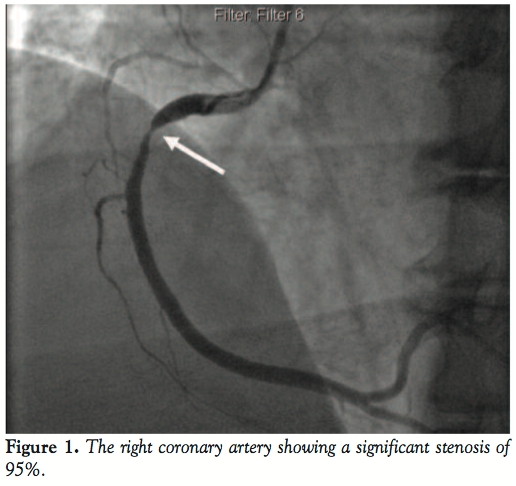

Coronary angiogram revealed a significantly tight stenosis of 95% in the proximal segment of the right coronary artery (RCA) with the other vessels having no significant disease (Figure 1). We treated the culprit vessel percutaneously by cannulating the RCA with a 7 Fr Judkins right guiding catheter (Figure 2) and using a 0.014” Galeo wire (Biotronik) to cross the lesion. The lesion was predilated with 3 mm x 10 mm Sprinter balloon (Medtronic) at 10 atm (Figure 3). However, just after withdrawing the balloon into the